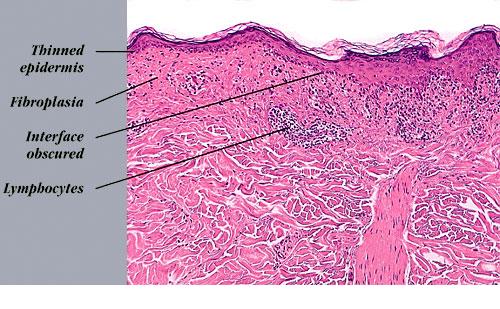

Atrophic lichen planus = الحزاز المنبسط الضموري